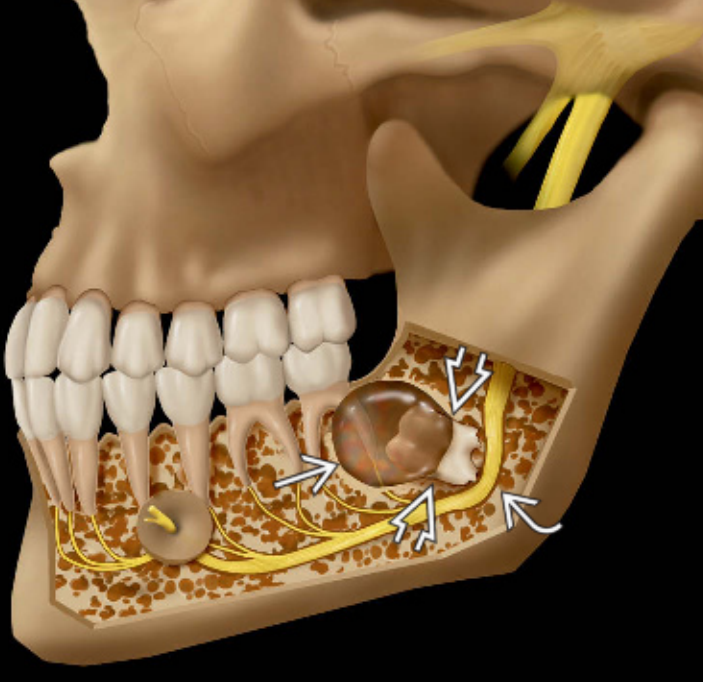

Μια περιακρορριζική κύστη αναπτύσσεται από ένα προϋπάρχον περιακρορριζικό κοκκίωμα. Τούτο ορίζεται ως ο εντοπισμένος, χρόνια φλεγμαίνων κοκκιώδης ιστός κοντά στο ακρορρίζιο ενός νεκρού δοντιού. Ο σχηματισμός της κύστης αποσκοπεί στην απομόνωση του φλεγμονώδους ερεθίσματος (νεκρός πολφός) από το οστό που περιβάλλει το δόντι και είναι το αποτέλεσμα της επιθηλιακής διαφοροποίησης.

Οι περιακρορριζικές κύστεις είναι συνήθως ασυμπτωματικές και αποκαλύπτονται τυχαία κατά τη λήψη περιακρορριζικών ακτινογραφιών νεκρών οδόντων. Μια περιακρορριζική κύστη δεν μπορεί εύκολα να διακριθεί ακτινογραφικά από ένα περιακρορριζικό κοκκίωμα.

Σε κύστεις που υπάρχουν για αρκετό χρονικό διάστημα μπορεί να παρατηρηθεί απορρόφηση της ρίζας του υπεύθυνου δοντιού ή γειτονικών δοντιών. Οι περιακρορριζικές κύστεις θεωρούνται μια από τις συχνότερες, αν όχι η συχνότερη, αιτία εμφάνισης διόγκωσης στις γνάθους. Συχνά οι ασθενείς δίνουν ιστορικό παρουσίας χρόνιας, βραδέως αυξανόμενης διόγκωσης, η οποία αρχικά είναι σκληρής συστάσεως ανάλογης οστού. Καθώς η κύστη αυξάνεται, και παρά την εναπόθεση νέου οστίτη ιστού, το οστικό τοίχωμα της κύστης λεπταίνει βαθμιαία και η διόγκωση δίνει την εντύπωση κελύφους αυγού. Μόνο όταν ραγεί το οστικό τοίχωμα της κύστης μπορεί να παρατηρηθεί κλυδασμός. Στην άνω γνάθο η διόγκωση μπορεί να επεκτείνεται τόσο παρειακά όσο και υπερώια, ενώ κατά κανόνα στην κάτω γνάθο η διόγκωση επεκτείνεται παρειακά.